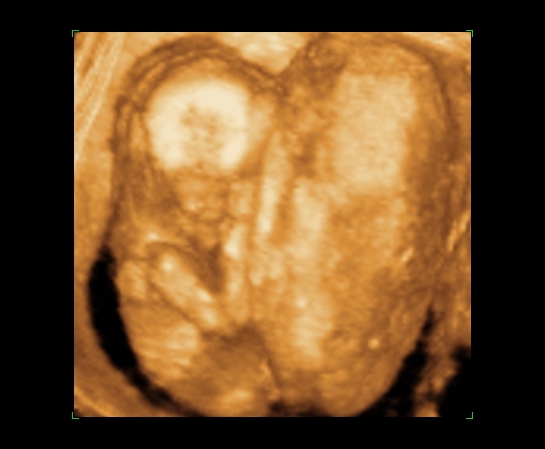

Csak gyors képek, mert pakolunk, a holnap meg rémes lesz, mert férjemnek még be kell mennie dolgozni, mielőtt indulunk :?

Lusta, kicsit kisebb a koránál, de gyönyörű, és lehet, hogy lány, de igazából nem lehetett látni, Annyira édes, inkább aludt volna :D